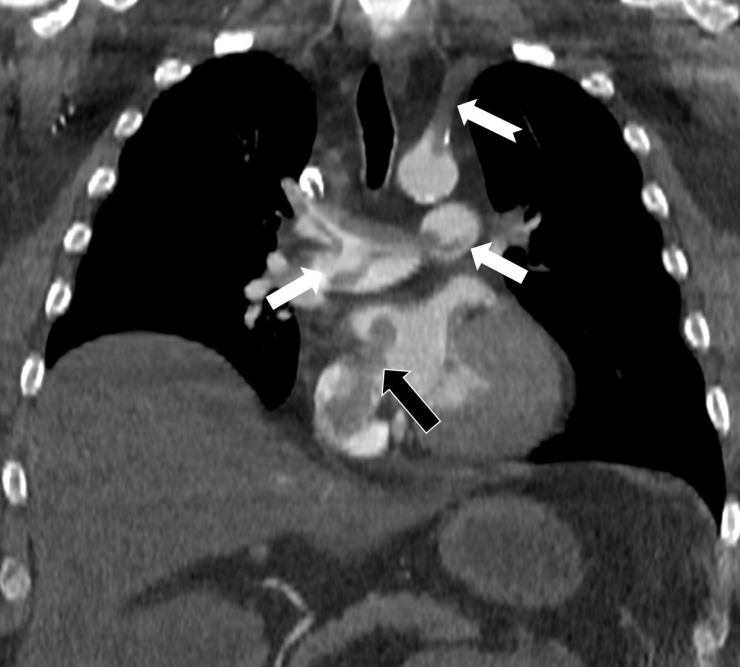

Kalp ve akciğer görüntülemesi alanındaki uluslararası bilimsel çalışmalarıyla tanınan Radyoloji Uzmanı Prof. Dr. Nevzat Karabulut, dünyanın önde gelen tıp dergilerinden Radiology dergisinin 2025 Kasım sayısında yayımlanan "Paradoxical Embolism with Clot-in-Transit in Atrial Septal Defect" adlı çalışmasında, penis ameliyatından 5 gün sonra ani göğüs ağrısı, nefes darlığı ve kol uyuşması şikâyetiyle hastaneye başvuran 60 yaşındaki bir hastada, daha önce fark edilmemiş kalp odacıkları arasındaki bir delikten geçen pıhtının hayati tehlike oluşturduğunu ortaya koydu.

Bir dönem Özel Denizli Tekden Hastanesi'nde de görev yapan Prof. Dr. Nevzat Karabulut'un yaptığı çalışmada; akciğerin bilgisayarlı tomografi anjiyografisi sayesinde toplar damarlardan kaynaklanan pıhtının akciğer damarlarını tıkaması yanında, kalpteki delik nedeniyle kalbin sağ tarafından sol tarafına geçerek ana atardamara ulaştığı ve sol kol damarını tıkadığı gösterildi.

Emboli görüntülemesi konusunda çok sayıda bilimsel çalışması bulunan Prof. Dr. Karabulut, genelde bacak damarlarından kaynaklanan pıhtıların ölümcül olabilen akciğer embolisine yol açması yanında, kalp deliği olan hastalarda ana atardamar yoluyla beyin, kol ve bacak gibi vücudun diğer bölgelerine de geçerek ani damar tıkanmasına (paradoks emboli) bağlı bulgulara yol açtığını belirtti. Prof. Dr. Karabulut'un çalışmasında nedeni bilinmeyen pıhtı atmalarında kalpteki gizli deliklerin mutlaka araştırılması gerektiği vurgulanarak ekokardiyografi ve bilgisayarlı tomografi tetkiklerinin erken ve doğru tanı koymada hayat kurtarıcı rolüne dikkat çekildi.